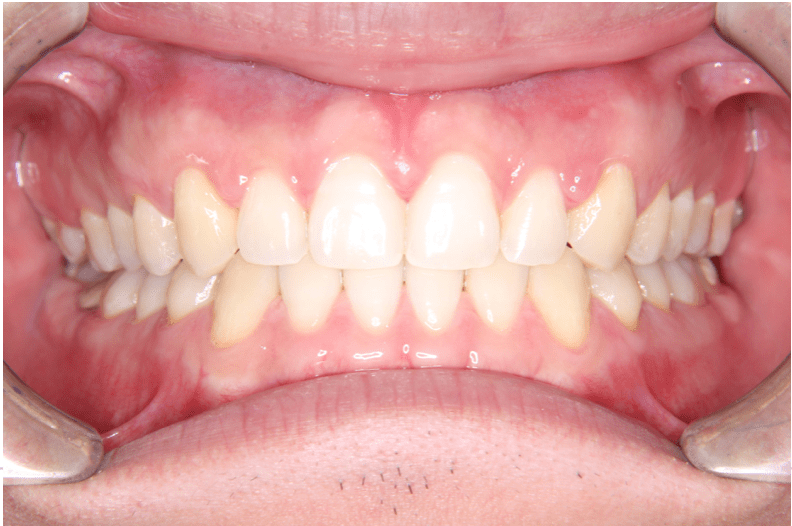

治療後(正面)

上下開いていた症例ですので、下を閉じてから上を閉じる計画を立てました。

症例情報:

【患者】 20代男性

【主訴】 前歯のすき間がきになる。

【診断】 空隙歯列

【抜歯の有無】 非抜歯

【治療期間】2年0ヶ月 通院回数15回

【治療内容】親知らずを抜歯した後、マウスピース型カスタムメイド矯正歯科装置(製品名インビザライン 完成物薬機法対象外)を使用して主訴である叢生の改善を行いました。

【費用】88万(税込)